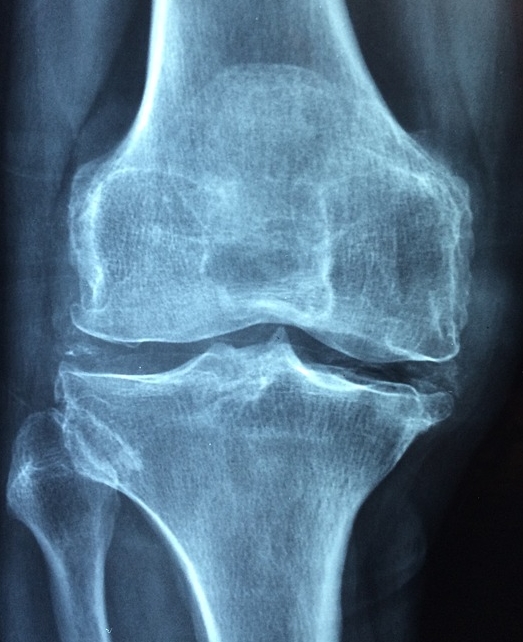

병원에서는 엑스레이로 관절 간격 변화를 확인하고, 초음파로 염증 부위를 세밀히 살피며, 혈액검사로 염증 수치나 자가항체 여부를 검사합니다. 제 지인은 무릎 통증이 있어 정형외과에 갔다가 단순 염증이 아니라 류마티스 관절염 초기라는 진단을 받고 바로 전문 치료를 시작했는데, 그 덕분에 지금까지 관절 변형 없이 잘 지내고 있습니다.

→ 병원에서는 먼저 환자의 증상과 병력을 꼼꼼히 확인합니다. 그 후 엑스레이 촬영으로 관절 간격이 줄어들었는지, 뼈 가장자리에 돌기가 생겼는지 확인합니다. 그러나 엑스레이만으로는 초기 염증을 놓칠 수 있어, 초음파로 관절 주위 부종과 활액막(관절을 감싸는 막)의 상태를 살펴봅니다. 류마티스 관절염이 의심되면 혈액검사로 염증 수치와 류마티스因자, 항CCP 항체 등을 검사합니다. 필요 시 MRI를 통해 연골 손상 정도나 미세한 변화를 더 정확히 확인하기도 합니다.